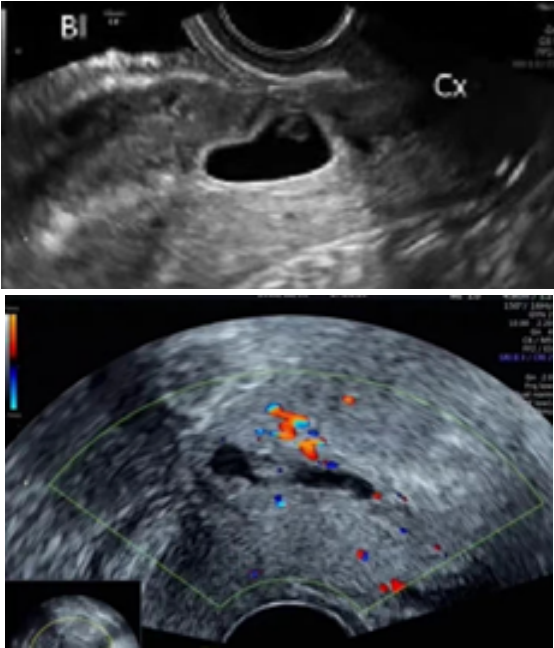

🔹II型

• 妊娠囊与膀胱间子宫肌层厚度≤3mm;

• 此型囊胚着床于缺损瘢痕的裂缺内。